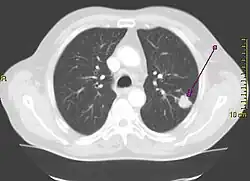

Le cancer du poumon peut être vu sur les radiographies thoraciques et le scanner. Le diagnostic est confirmé par une biopsie. Ceci se fait généralement par bronchoscopie, ou par biopsie guidée par scanner. Le traitement et le pronostic dépendent du type histologique du cancer, de son stade (degré de dissémination), et de l'état général de santé du patient.

La radiographie thoracique est la première mesure à prendre si un patient se plaint de symptômes pouvant suggérer un cancer du poumon. Ceci peut révéler une masse évidente, un élargissement du médiastin (qui suggère une extension aux ganglions lymphatiques qui s'y trouvent), une atélectasie (affaissement), une inflammation (pneumonie) ou un épanchement pleural. En l'absence de signes radiographiques, mais si les soupçons sont élevés (par exemple, un gros fumeur avec hémoptysie), une bronchoscopie ou un scanner peuvent donner l'information nécessaire. La bronchoscopie ou la biopsie guidée par scanner sont souvent utilisées pour identifier le type de tumeur[3].

Si les examens confirment le cancer du poumon, le scanner et souvent la tomographie par émission de positons (TEP) sont utilisés pour déterminer si le cancer est localisé et possible à traiter par chirurgie, ou bien s'il s'est étendu au point de ne plus pouvoir être éliminé par la chirurgie. Des tests sanguins et la spirométrie (test de la fonction respiratoire) sont également nécessaires pour déterminer si le patient va assez bien pour supporter l'opération. Si la spirométrie révèle une faible réserve respiratoire (souvent due à un trouble ventilatoire obstructif), la chirurgie peut être contre-indiquée.